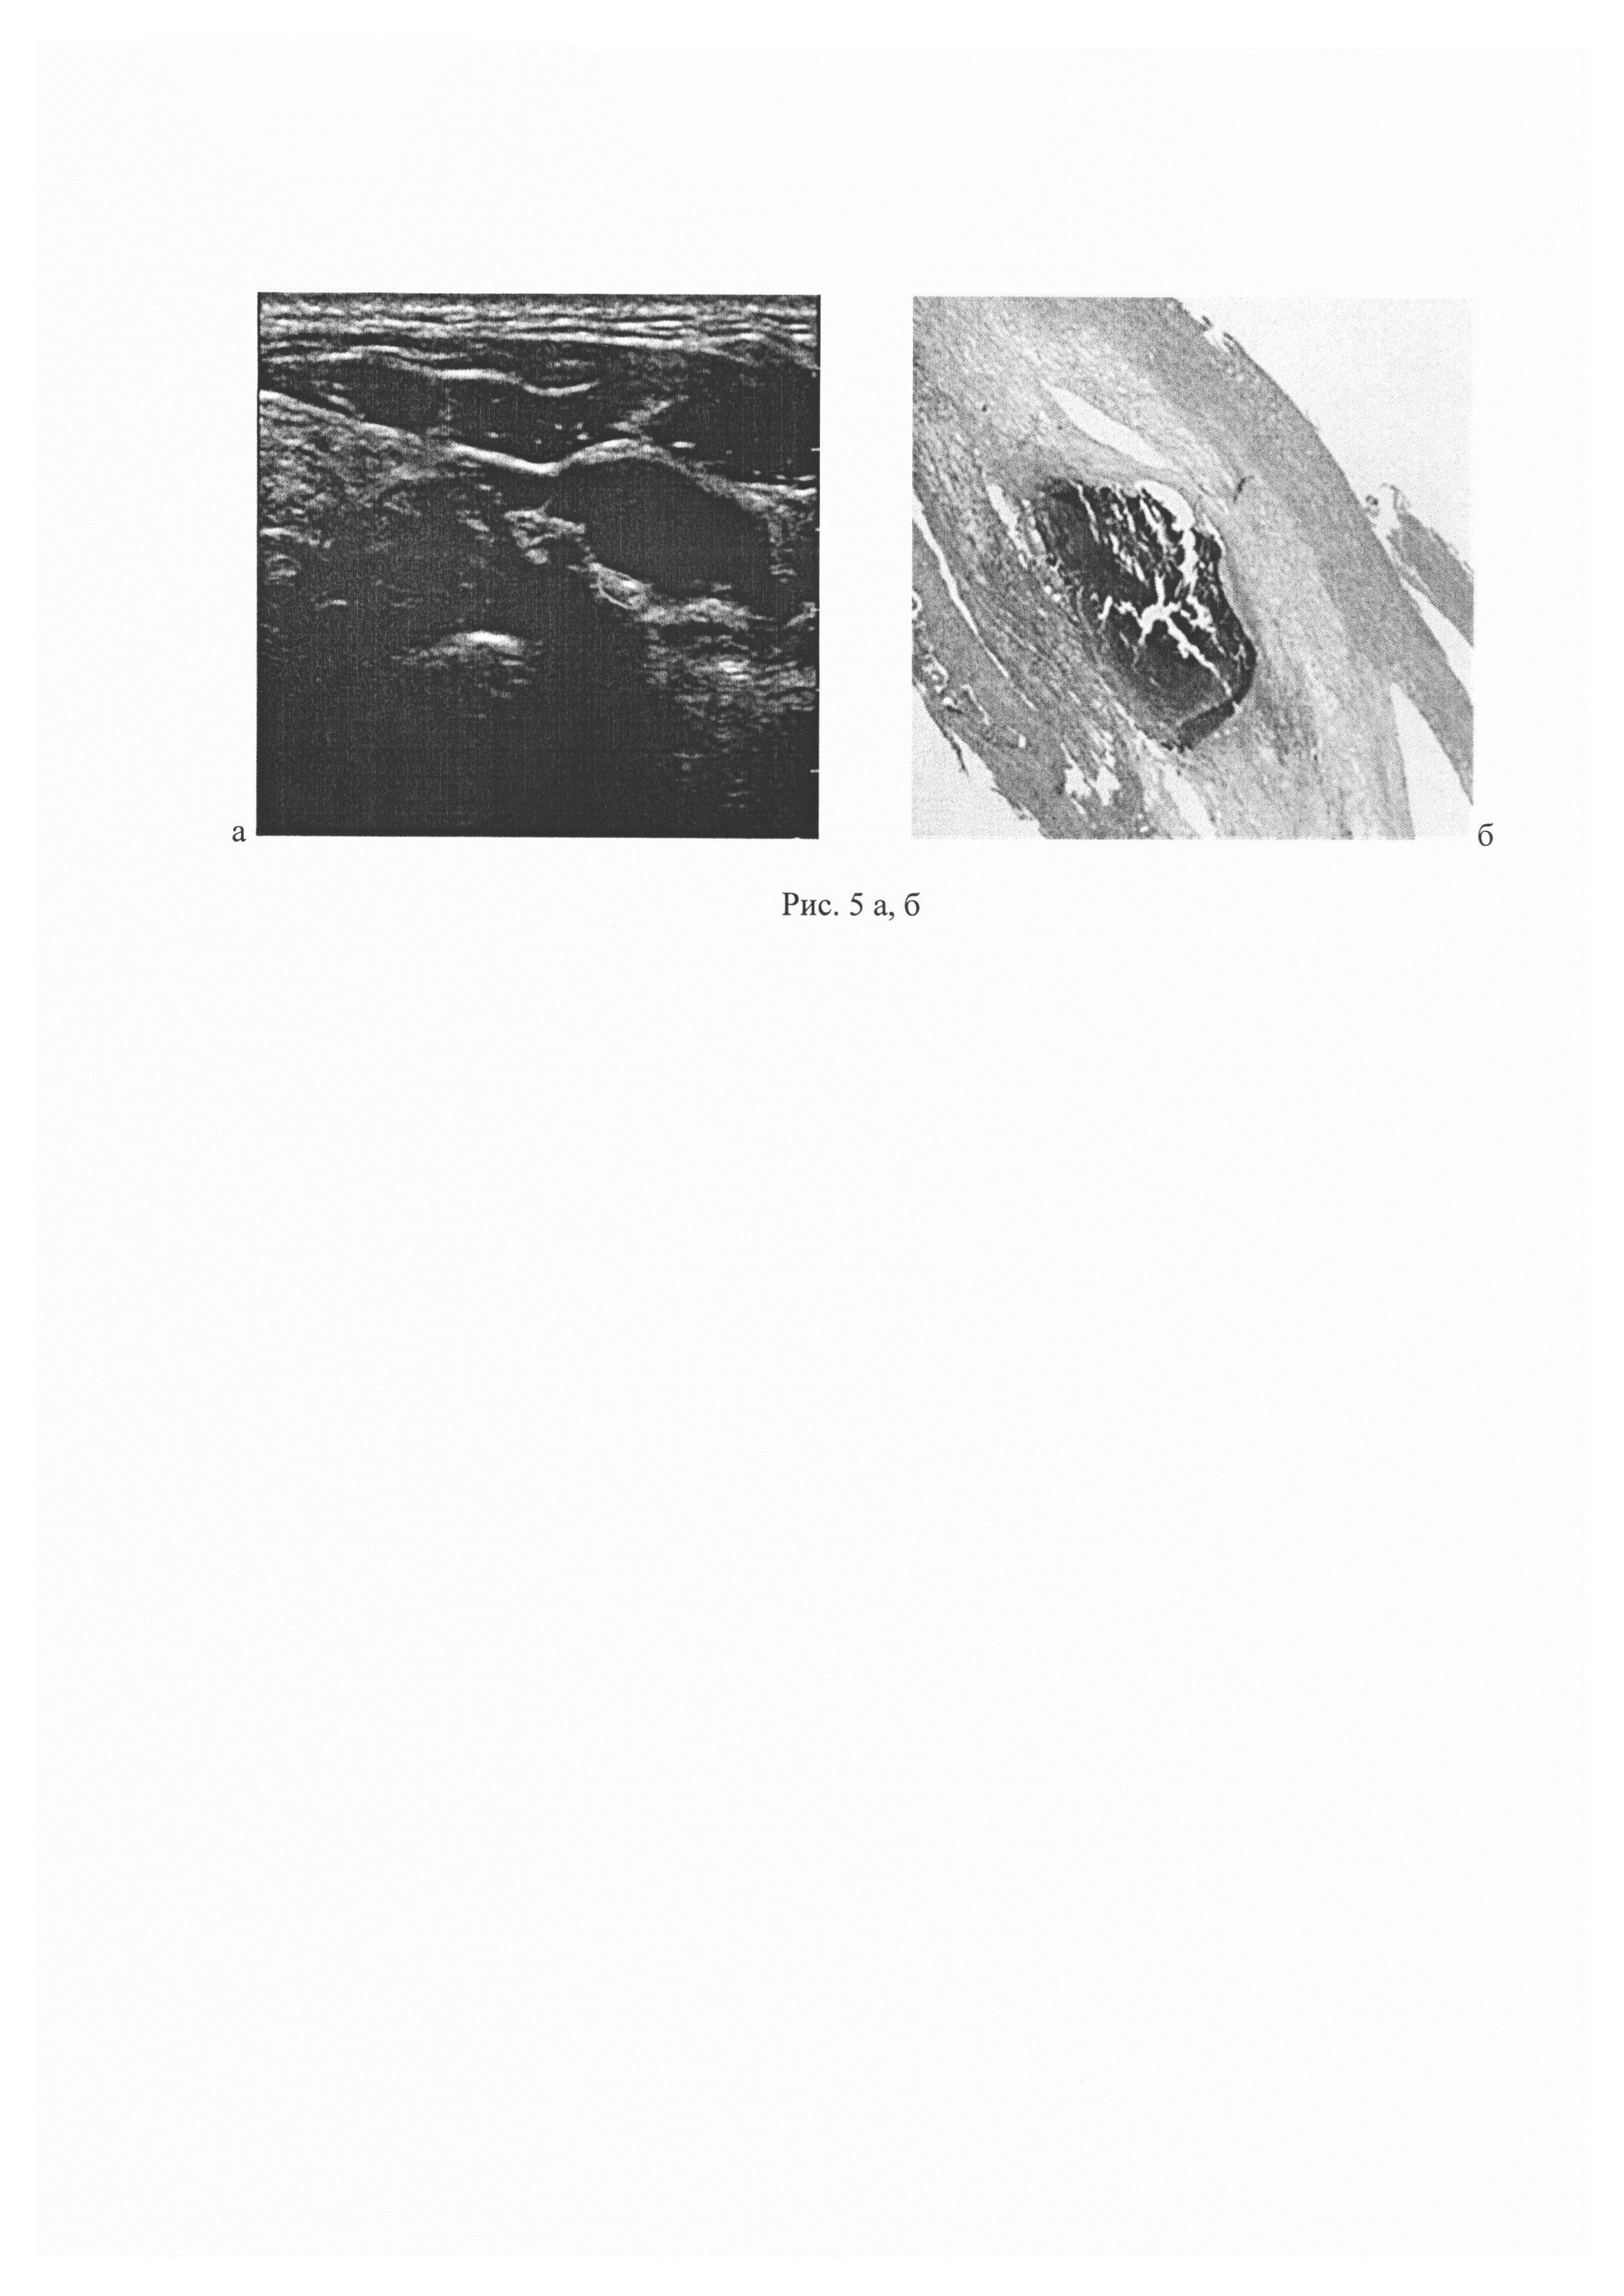

Изобретение относится к области медицины, в частности к неврологии и может быть использовано для определения структуры и морфологических особенностей атеросклеротической бляшки (АСБ). В развитии нарушений мозгового кровообращения (НМК) в каротидной системе мозга важна не только степень стеноза каротидного синуса (КС), но и структура АСБ: наличие прогрессирующего атероматоза на фоне воспалительного процесса, истончение и разрушение покрышки бляшки, инфильтрация бляшки макрофагами и другими клетками, деструктивные изменения вновь образованных сосудов с развитием кровоизлияний в бляшку. Эти процессы в АСБ повышают риск увеличения стеноза КС и его тромбоза, а также эмболии дистальных отделов внутренней сонной артерии (ВСА) и ее ветвей, что в конечном счете приводит к тяжелому НМК с развитием инфаркта мозга. Одним из наиболее эффективных методов предотвращения НМК в системе ВСА является каротидная эндартерэктомия (КЭЭ) - операция удаления АСБ из КС. Для оценки риска возникновения НМК и решения вопроса о показаниях к КЭЭ широко используется ультразвуковое исследование сонных артерий, позволяющее определить степень стеноза КС, а также эхоструктуру АСБ, отражающую их морфологический состав. В последние годы обсуждается необходимость (независимо от степени стеноза КС) проведения КЭЭ при наличии ультразвуковых признаков «нестабильной» структуры бляшки как у больных с перенесенным НМК, так и у пациентов с асимптомным стенозом (Madieke I.L., Fiona K., Bonati L.H., et al. Investigations of Carotid Stenosis to Identify Vulnerable Atherosclerotic Plaque and Determine Individual Stroke Risk. Circulation. 2017; 81: 1246-53). С внедрением технологии количественного анализа компьютерных изображений появились новые возможности и для изучения структуры АСБ [Tegos T.J., Sohail М., Sabetai М.М., et al. Echomorphologic and histopathologic characteristics of unstable carotid plaques. Am. J. Neuroradiol. 2000; 21: 1937-44]. Разработана и методика сопоставления структуры и морфологических особенностей АСБ. Такие исследования, несмотря на их важность, все еще немногочисленны. Известен количественный метод определения однородности структуры атеросклеротической бляшки с помощью медианы серой шкалы или GSM (grey scale median). Изображения атеросклеротических бляшек, полученных с помощью стандартного УЗ-исследования в серой шкале, подвергались последующей компьютерной обработке. Осуществлялось количественное определение интенсивности (или эхогенности) атеросклеротической бляшки. При этом на изображении выбирались референсные зоны, такие как просвет сосуда (которому соответствует значение GSM 0-5) и его адвентициальный слой (GSM 185-195). Затем проводилось нормирование изображения и оценивалась эхогенность бляшки. По соотношению участков с низкой (GSM<50) или высокой (GSM>50) эхогенностью определяли однородность АСБ (М.М. Sabetai, T.J. Tegos, A.N. Nicolaides, S. Dhanjil, G.J. Pare and J.M. StevensReproducibility of Computer-Quantified Carotid Plaque Echogenicity: Can We Overcome the Subjectivity? Stroke. 2000; 31:2189-2196). Недостатками способа является его использование только для выяснения однородности АСБ. Известен способ определения структурных характеристик атеросклеротической бляшки сонных артерий посредством ультразвукового исследования в В-режиме, режиме тканевой гармоники и режиме недопплеровской визуализации кровотока и сравнения этих данных с данными гистологического исследования (Тимина И.Е., Бурцева Е.А., Скуба Н.Д. и др. Сопоставление структуры атеросклеротической бляшки в сонной артерии по данным комплексного ультразвукового и гистологического исследований. Ультразвуковая и функциональная диагностика, 2004, №3, с. 81-87). Однако способ не обладает достаточной точностью в отношении структурных характеристик атеросклеротической бляшки сонных артерий из-за отсутствия стандартизации протокола измерений. Данный источник информации рассмотрен в качестве ближайшего аналога. Технический результат заключается в повышении точности определения структурных характеристик атеросклеротической бляшки сонных артерий, за счет стандартизации протокола измерений позволяющего минимизировать их погрешность. Технический результат достигается тем, что определение структурных характеристик атеросклеротической бляшки сонных артерий проводят путем ее ультразвукового исследования, при этом ультразвуковое исследование атеросклеротической бляшки проводят на глубине 5,0-10,0 мм в области наибольшего сужения просвета сонной артерии в продольной и поперечной проекциях в В-режиме с использованием линейного датчика с частотой излучения 11 МГц, со средней частотой кадров и максимальным динамическим диапазоном 60 дБ, затем на полученных неподвижных кадрах выделяют участки атеросклеротических бляшек размером до 1 см, и посредством программного обеспечения ультразвуковой системы, вычисляют медиану интенсивности ультразвукового сигнала в децибелах (дБ), отраженного от исследуемых участков атеросклеротической бляшки и при значении интенсивности ультразвукового сигнала 1,1-8,0 дБ определяют в атеросклеротической бляшке очаги атероматоза, 9,0-22,0 - очаги атероматоза с многочисленными кристаллами холестерина, 23,0-31,0 - очаги фиброза с диффузно расположенными липофагами и/или сосудами, 32,0-39,0 - очаги фиброза с кальцификатами, 40,0-45,0 - очаги кальциноза. Способ осуществляется следующим образом. Ультразвуковое исследование атеросклеротической бляшки выполняют на приборе Phillips iE33 на глубине 5,0-10,0 мм в продольной и поперечной проекциях. Исследование выполняют в серошкальном режиме (В-режим) с использованием линейного датчика с частотой излучения 11 МГц, со средней частотой кадров и максимальным динамическим диапазоном (60 дБ). Перед проведением каждого исследования устанавливают стандартные настройки ультразвуковой системы (настройки дисплея, цветовые эффекты, мощность, частота излучения). На неподвижных кадрах выделяют (обрисовывают) наиболее информативные, с точки зрения эхогенных характеристик, участки бляшек, размером до 1 см, расположенные в области наибольшего сужения просвета артерии. Далее с помощью программного обеспечения ультразвуковой системы вычисляют медиану интенсивности (в децибелах, дБ) ультразвукового сигнала, отраженного от исследуемых участков АСБ. Все изображения участков АСБ в В-режиме преобразовывают в формат JPG. При значении интенсивности ультразвукового сигнала 1,1-8,0 дБ определяют в атеросклеротической бляшке очаги атероматоза, 9,0-22,0 - очаги атероматоза с многочисленными кристаллами холестерина, 23,0-31,0 - очаги фиброза с диффузно расположенными липофагами и/или сосудами, 32,0-39,0 - очаги фиброза с кальцификатами, 40,0-45,0 - очаги кальциноза. В данное проспективное поисковое исследование были включены 90 пациентов (71 мужчина и 19 женщин, медиана возраста 62 (47-79) года), наблюдавшихся в отделении общей ангионеврологии Научного центра неврологии (Москва) за период с апреля 2015 г. по март 2016 г. У всех больных с помощью ультразвукового исследования сонных артерий был установлен атеросклеротический стеноз КС, измеренный по алгоритму исследования ECST [European Carotid Surgery Trialist's Collaborative Group. Randomised trial of endarterectomy for recently symptomatic carotid stenosis: final results of the MRC European Carotid Surgery Trial (ECST). Lancet. 1998; 351: 1379-87], и выполнена КЭЭ. Ультразвуковое исследование АСБ выполнялось на приборе Phillips iE33 на глубине 5,0-10,0 мм в области наибольшего сужения просвета сонной артерии в продольной и поперечной проекциях в В-режиме с использованием линейного датчика с частотой излучения 11 МГц, со средней частотой кадров и максимальным динамическим диапазоном 60 дБ,. Стандартизация протокола измерений позволяет минимизировать возможную погрешность измерений. Результаты ультразвукового исследования структуры АСБ сопоставлялись с результатами морфологического исследования АСБ, удаленных при КЭЭ. Для оценки морфологической структуры АСБ в целом и отдельных ее участков, тех, для которых интенсивность сигнала была установлена до оперативного вмешательства, каждая бляшка разрезалась на блоки толщиной 0,3-0,5 см в плоскости, перпендикулярной продольной оси артерии. С каждого блока, залитого в парафин, получали серийные срезы толщиной 5-6 мкм, которые окрашивали гематоксилином и эозином по методу ван Гизона. Для выявления эластических волокон, соединений железа, извести и фибрина в бляшках срезы дополнительно окрашивались по методам Вейгерта, Перльса, Коссы и Шуенинова соответственно. При микроскопическом исследовании структуры каждой АСБ оценивалась по 24 компонентам и процессам: очагам атероматоза, фиброза, кальциноза, отека и некроза волокнистых структур, наличию липофагов, вновь образованных сосудов, очагов кровоизлияний, истончению и изъязвлению покрышки бляшки, тромбам на ее поверхности и др. Определялись соотношение в срезах АСБ площади очагов атероматоза, фиброза и кальциноза, а также количество (степень выраженности) других компонентов (малое, умеренное, большое). Статистическая оценка однородности сравниваемых групп проводилась с применением критерия Краскела-Уоллиса (с последующим post-hoc-анализом). Для расчетов использовался статистический пакет SAS 9.4. Атеросклеротический стеноз КС у одной группы исследованных пациентов протекал симптомно (симптомные пациенты), у другой - асимптомно (асимптомные пациенты). К асимптомным пациентам мы относили тех пациентов, у которых не было анамнестических данных за наличие нарушений мозгового кровообращения в системе стенозированной ВСА в течение последних 6 месяцев, а также на ипсилатеральной (по отношению к стенозу) стороне головного мозга отсутствовали клинические симптомы церебральной или ретинальной ишемии. Пациенты, перенесшие за последние полгода те или иные формы ишемического НМК (в рассматриваемом сосудистом бассейне), расценивались как симптомные. Пациентов с асимптомным течением (среди исследованных 90 человек) было более чем в 2 раза больше, в сравнении с пациентами с симптомным течением: 62 (69%) к 28 (21%). Это соотношение среди исследованных пациентов в известной степени оценивает соответствующее соотношение и в популяции людей с атеросклеротическим стенозом КС в целом. Распределение пациентов (n=90) в зависимости от структуры АСБ, степени стеноза КС и клинических проявлений цереброваскулярной недостаточности представлено в таблице 1. С целью определения количественных ультразвуковых значений интенсивности от определенных компонентов АСБ в 37 из них микроскопически исследовано от 1 до 4 участков (всего 67 участков размером до 10 мм). Анализ микроскопического исследования 67 участков размером до 10 мм АСБ, выбранных для количественной ультразвуковой оценки, позволил установить, что в 29 из них были выявлены очаги атероматоза, в том числе в 17 - очаги с частичным кальцинозом жиро-белкового детрита, в 12 - очаги с многочисленными кристаллами холестерина среди атероматозных масс. В 34 участках были выявлены очаги фиброзной ткани, при этом в 6 участках содержались очаги с диффузно расположенными липофагами и в 5 участках с диффузно расположенными сосудами, в 13 - большие их скопления, а в 10 участках очаги фиброза наряду с отдельными липофагами и/или сосудами определялись небольшие кальцификаты. Остальные 4 участка представляли собой крупные очаги кальциноза. Результаты сопоставления количественной ультразвуковой оценки участков АСБ с их морфологической структурой представлены в таблице 3. В результате сопоставления были определены статистически значимо различающиеся диапазоны значений интенсивности ультразвукового сигнала для очагов атероматоза, очагов атероматоза с многочисленными кристаллами холестерина, очагов фиброза с диффузно расположенными липофагами и/или вновь образованными сосудами, очагов фиброза с кальцификатами и очагов кальциноза: 1,1-8,0 дБ, 9,0-22,0 дБ, 23,0-31,0 дБ, 32,0-39,0 дБ и 40,0-45,0 дБ соответственно (приведены значения от 15-й до 85-й процентили). Все варианты АСБ по интенсивности отраженного ультразвукового сигнала различаются статистически значимо. В качестве примеров представлены ультразвуковые и морфологические исследования образцов атеросклеротических бляшек пациентов с ишемическим НМК. Примеры выполнения способа. Образец 1. Ультразвуковая и морфологическая характеристика основных компонентов АСБ показана на рис. 1а, б: а - выделенный участок с интенсивностью ультразвукового сигнала до 2 дБ; б - очаг атероматоза (указан стрелкой), соответствующий участку на ультразвуковом изображении (гистологический срез АСБ, окраска гематоксилином и эозином, увеличение ×40). Образец 2. Ультразвуковая и морфологическая характеристика основных компонентов АСБ показана на рис. 2а, б: а - выделенный участок с интенсивностью ультразвукового сигнала 10 дБ; б - очаг атероматоза с многочисленными кристаллами холестерина (указан стрелкой), соответствующий участку на ультразвуковом изображении (гистологический срез АСБ, окраска гематоксилином и эозином, увеличение ×40). Образец 3. Ультразвуковая и морфологическая характеристика основных компонентов АСБ показана на рис. 3а, б: а - выделенный участок с интенсивностью ультразвукового сигнала 23 дБ; б - очаг фиброза с диффузно расположенными липофагами (указан стрелкой), соответствующий участку на ультразвуковом изображении (гистологический срез АСБ, окраска гематоксилином и эозином, увеличение ×40). Образец 4. Ультразвуковая и морфологическая характеристика основных компонентов АСБ показана на рис. 4а, б: а - выделенный участок с интенсивностью ультразвукового сигнала 32 дБ; б - очаг фиброза с кальцификатами (указан стрелкой), соответствующий участку на ультразвуковом изображении (гистологический срез АСБ, окраска гематоксилином и эозином, увеличение ×40). Образец 5. Ультразвуковая и морфологическая характеристика основных компонентов АСБ показана на рис. 5а, б: а - выделенный участок с интенсивностью ультразвукового сигнала 40 дБ; б - очаг кальциноза (указан стрелкой), соответствующий участку на ультразвуковом изображении (гистологический срез АСБ, окраска гематоксилином и эозином, увеличение ×40).